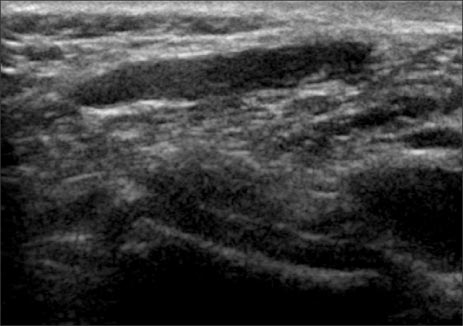

Fig. 2

Perineal ultrasonography reveals hypoechoic tubular mass without any communication between the mass and other organ.